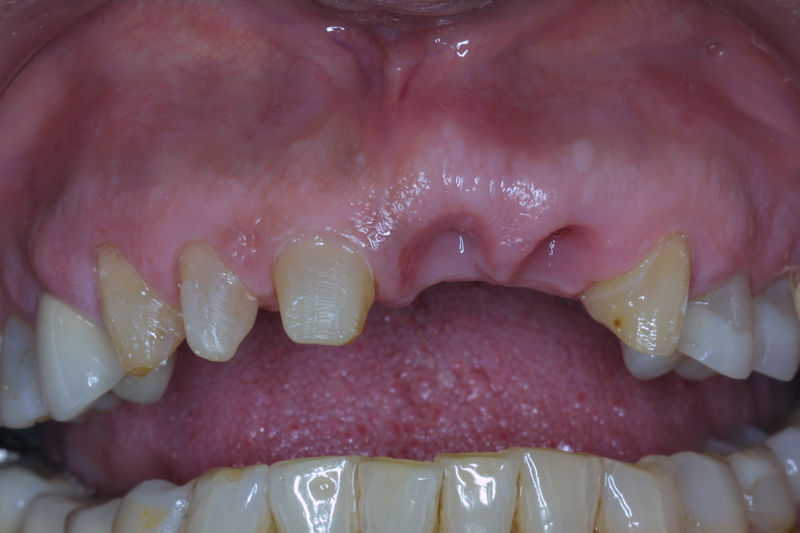

Implante fracasado, extracción, carillas, coronas y prótesis fija.